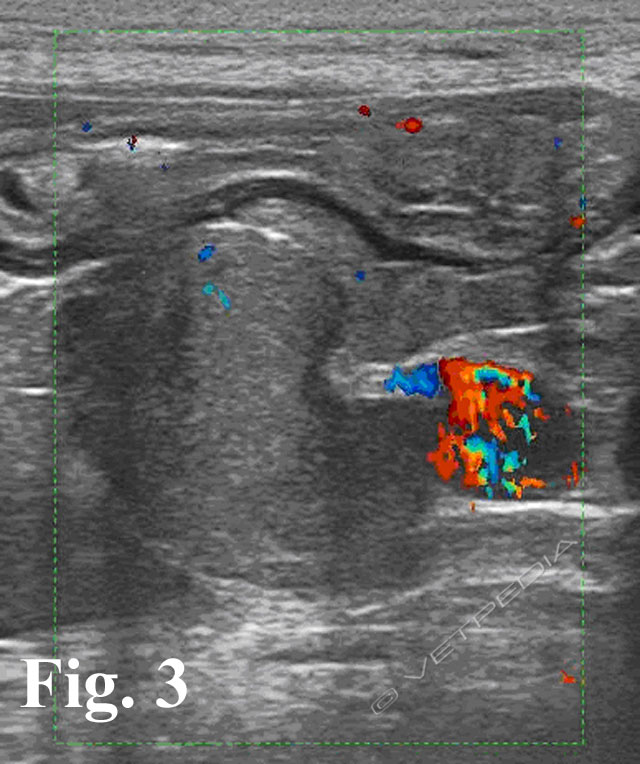

{{/_source.additionalInfo}}L’ecografia rappresenta una delle metodiche più sensibili per lo studio dei linfonodi addominali e permette di studiare la loro forma, le dimensioni, l’ecostruttura e l’ecogenicità. In tabella 1 sono riportati i linfonodi che drenano gli organi viscerali e le strutture parietali1. LINFONODI VISCERALI LINFONODI PARIETALI Lin